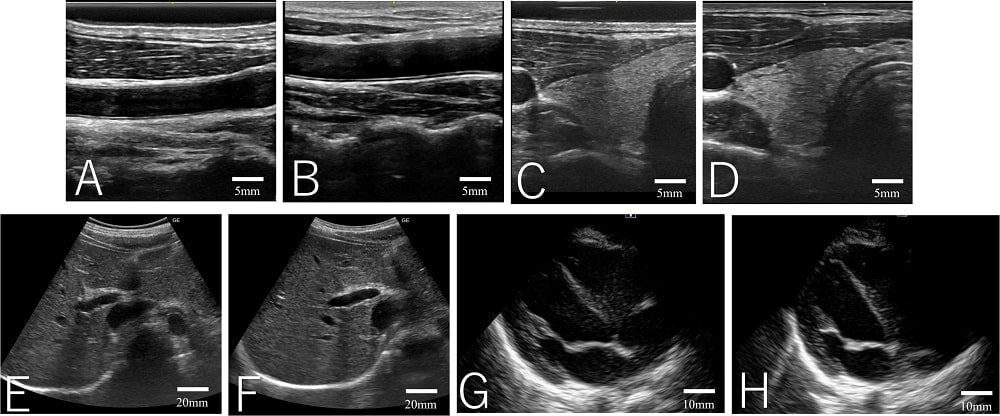

Гелю для УЗИ нашли твердую альтернативу

Медики из Японии разработали подушечку, которая выполняет те же функции, что и гель для ультразвуковых исследований, но более удобна для доктора и комфортна для пациента. В качестве материала использовали в том числе семена тропического бобового дерева — «индийского финика» тамаринда. В последние годы появилось множество разработок, которые значительно повысили качество медицинского обслуживания. Среди них есть и инновации в области ультразвуковых исследований (УЗИ), например карманный аппарат, подключающийся к смартфону.